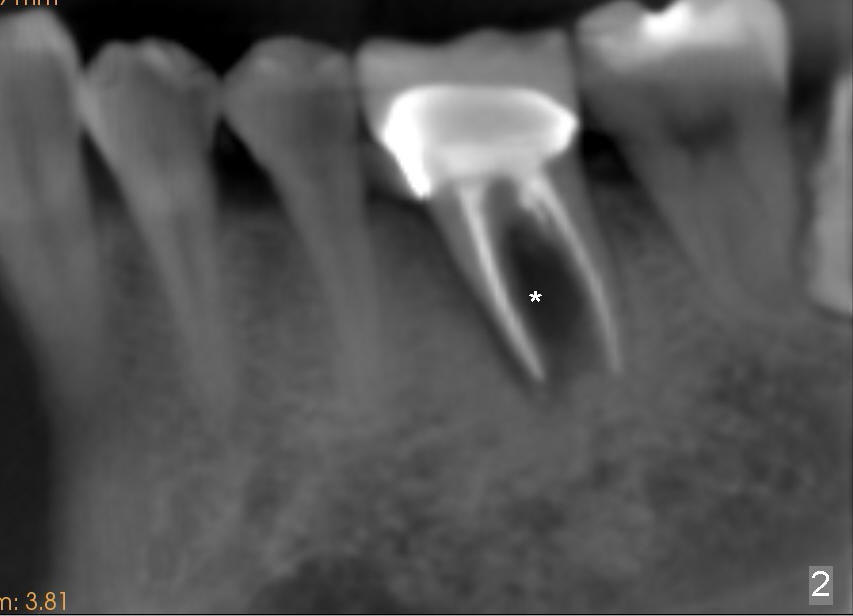

A 41-year-old man has discomfort in the lower left 1st molar. Exam shows swelling and a fistula in the mesiobuccal gingiva (Fig.1 >) and large radiolucency around the mesial root (Fig.2 *). After extraction and thorough debridement, osteotomy is initiated in the mesial socket, but the upper portion of the reamer (Fig.3 R, 2.5 mm) is placed in the middle of the edentulous space. By the time 5 mm reamer is removed, the osteotomy (Fig.4 O) forms mainly in the mesial socket with the septum (S) deviated to the distal socket. A 7x17 mm tap is placed with stability (Fig.5 T). An implant with the same dimension is placed with insertion torque more than 60 Ncm (Fig.6 I). With the large implant, two proximal sutures are able to close the remaining socket gaps (Fig.7). The swelling and fistula disappears and the gingiva tightly surrounds the implant in 1 week postop (Fig.8).